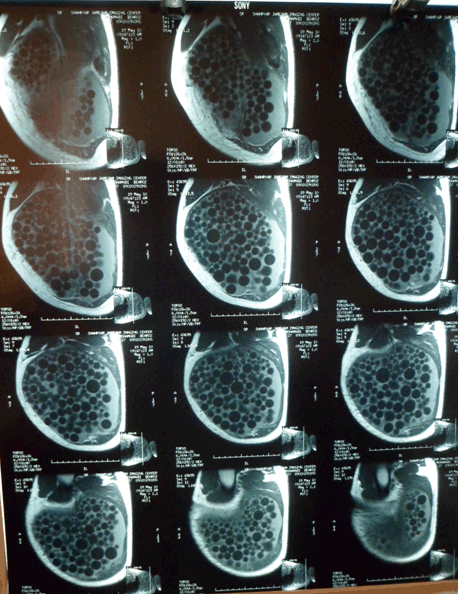

A 30-year-old man, a taxi driver, presented with a large painless, slowly growing mass in his left armpit for approximately three years. He was diagnosed in the same location with an axillary hydatid cyst four years ago and was surgically treated. He also had a history of a successful craniotomy when he was nine years old due to CHD, but no document to support it. Physical examination revealed a 20x8 cm dense, semi-mobile painless mass in the left axillary fossa and conserved range of motion in the left glenohumeral joint Serology test (ELISA) for Echinococcosis was positive. MRI scan showed a large multicystic intramuscular mass in inferior tip of the left scapula and in the dorsal thoracic muscles invading the deltoid, infraspinatus, teres major and teres minor muscles as shown in Figure 1. CT scan and sonography for whole body did not show any other involvements. The diagnosis was relatively easy; by his past medical history, imaging data and endemic context. The patient was given albendazole preoperatively for three months. Under general anesthesia, en bloc resection was successfully performed. The specimen was macroscopically two pieces of creamy brown colored membranous soft tissue and multiple small cysts. The membranous tissues were each measuring 23×9×6 cm and 8×4.5×0.5 cm. The cysts measured 1 to 1.7 cm in diameters. Microscopically, cystic walls composed of inner germinal layer and outer fibrous laminar (chitinous) layer surrounded by fibrous capsule. Daughter cysts and protoscolices were also seen. Figure 2 indicates sagittal section of the MRI through the lesion. The images are compatible with type CE2 of the cyst according to WHO classification appearing as honeycomb pattern. The patient was sent home with adjunctive albendazole chemotherapy (15 mg/kg/day) for three months. | ||||||